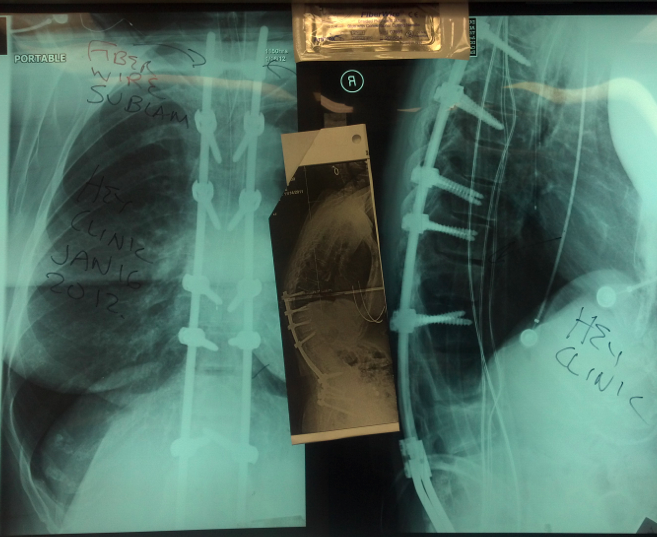

From heyclinic.com

Kyphosis surgery today for Proximal Junctional Kyphosis (PJK) with new fiber wire technique to Best Kyphosis Surgeon In this procedure, the surgeon uses metal rods. At nyu langone, orthopedic surgeons and neurosurgeons are specially trained to correct spinal curvature caused by scoliosis or. Mayo clinic doctors and researchers are studying ways to improve the diagnosis and treatment of kyphosis. Primary care physicians are often the first to treat symptoms of back pain. Your northwestern medicine orthopaedic team. Best Kyphosis Surgeon.